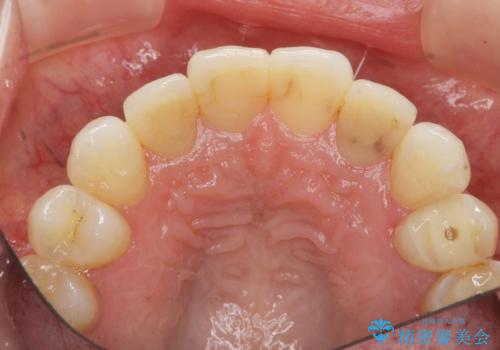

- 前医に前歯の吸収による抜歯の必要性を伝えられ、前歯の審美的な改善・治療を求めて来院されました。

CT撮影を行った結果、右上前歯は吸収が進み抜歯が必要な状態です、

抜歯をせず放置すると、より吸収が進み臨在する歯にも悪影響を及ぼしてしまう可能性が考えられます。

上顎4前歯は、根管治療の既往があり、虫歯も見られたことからブリッジによる治療で審美性の回復を行うとともに臨在歯の虫歯もセラミック治療を行っていきます。